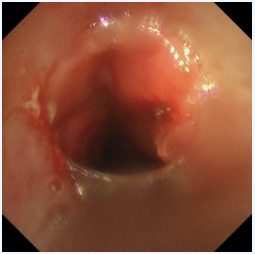

冷冻修复,深度“清创”:随后,应用冷冻探头对残余的增生组织及基底进行冻融治疗。极低温的探头接触组织,能使其变性、坏死并最终脱落,同时还能有效止血、减少瘢痕形成。这一步骤如同为气道进行一次深度的“保养与清洁”,能更彻底地清除病灶,降低复发风险。

两种技术优势互补,相得益彰,在微小创伤的前提下,实现了对复杂气道狭窄的最大化疏通。